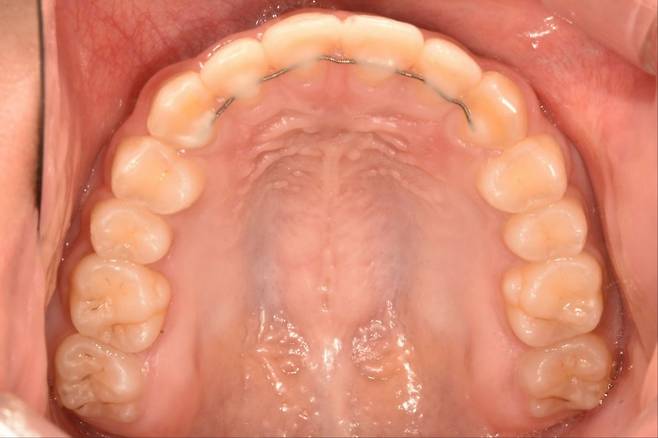

고정식 유지장치는 교정 치료를 종료하기 전 또는 직후에 얇은 철사를 앞니 안쪽에 붙이는데, 겉으로는 잘 보이지 않는다. 교정 치료를 끝낸 직후, 앞니 치아 배열은 흐트러지기 쉬워 고정식 유지장치로 치열을 유지한다.

고정식 유지장치는 치아에 붙어있어 환자가 임의로 제거할 수 없다. 처음에는 다소 이물감을 느낄 수 있지만 대개 일찍 적응해 거의 불편감을 느끼지 못하게 된다. 착용에 신경 쓸 필요가 없어 편리하지만, 구강위생 관리가 소홀할 경우 장치 주변에 음식물이 남아 치석이 생기는 경우가 있다. 특히 침이 나오는 부분과 가까운 아래 앞니 유지장치 주위에 치석이 생기는 경우가 많아, 양치질 시 꼼꼼히 닦아야 한다.

고정식 유지장치 철사는 탄성이 있고, 잘 변형되지 않아 일상에서 망가지는 경우는 거의 없지만, 지나치게 단단한 음식물을 섭취할 경우 강한 외력에 철사가 탈락하거나 변형될 수 있다. 고정식 유지장치가 부착된 부위는 치실을 일반적인 방법으로 사용하기 어렵고, 잘못 사용해 철사에 무리한 힘을 주게 되면 장치가 변형될 우려가 있다.